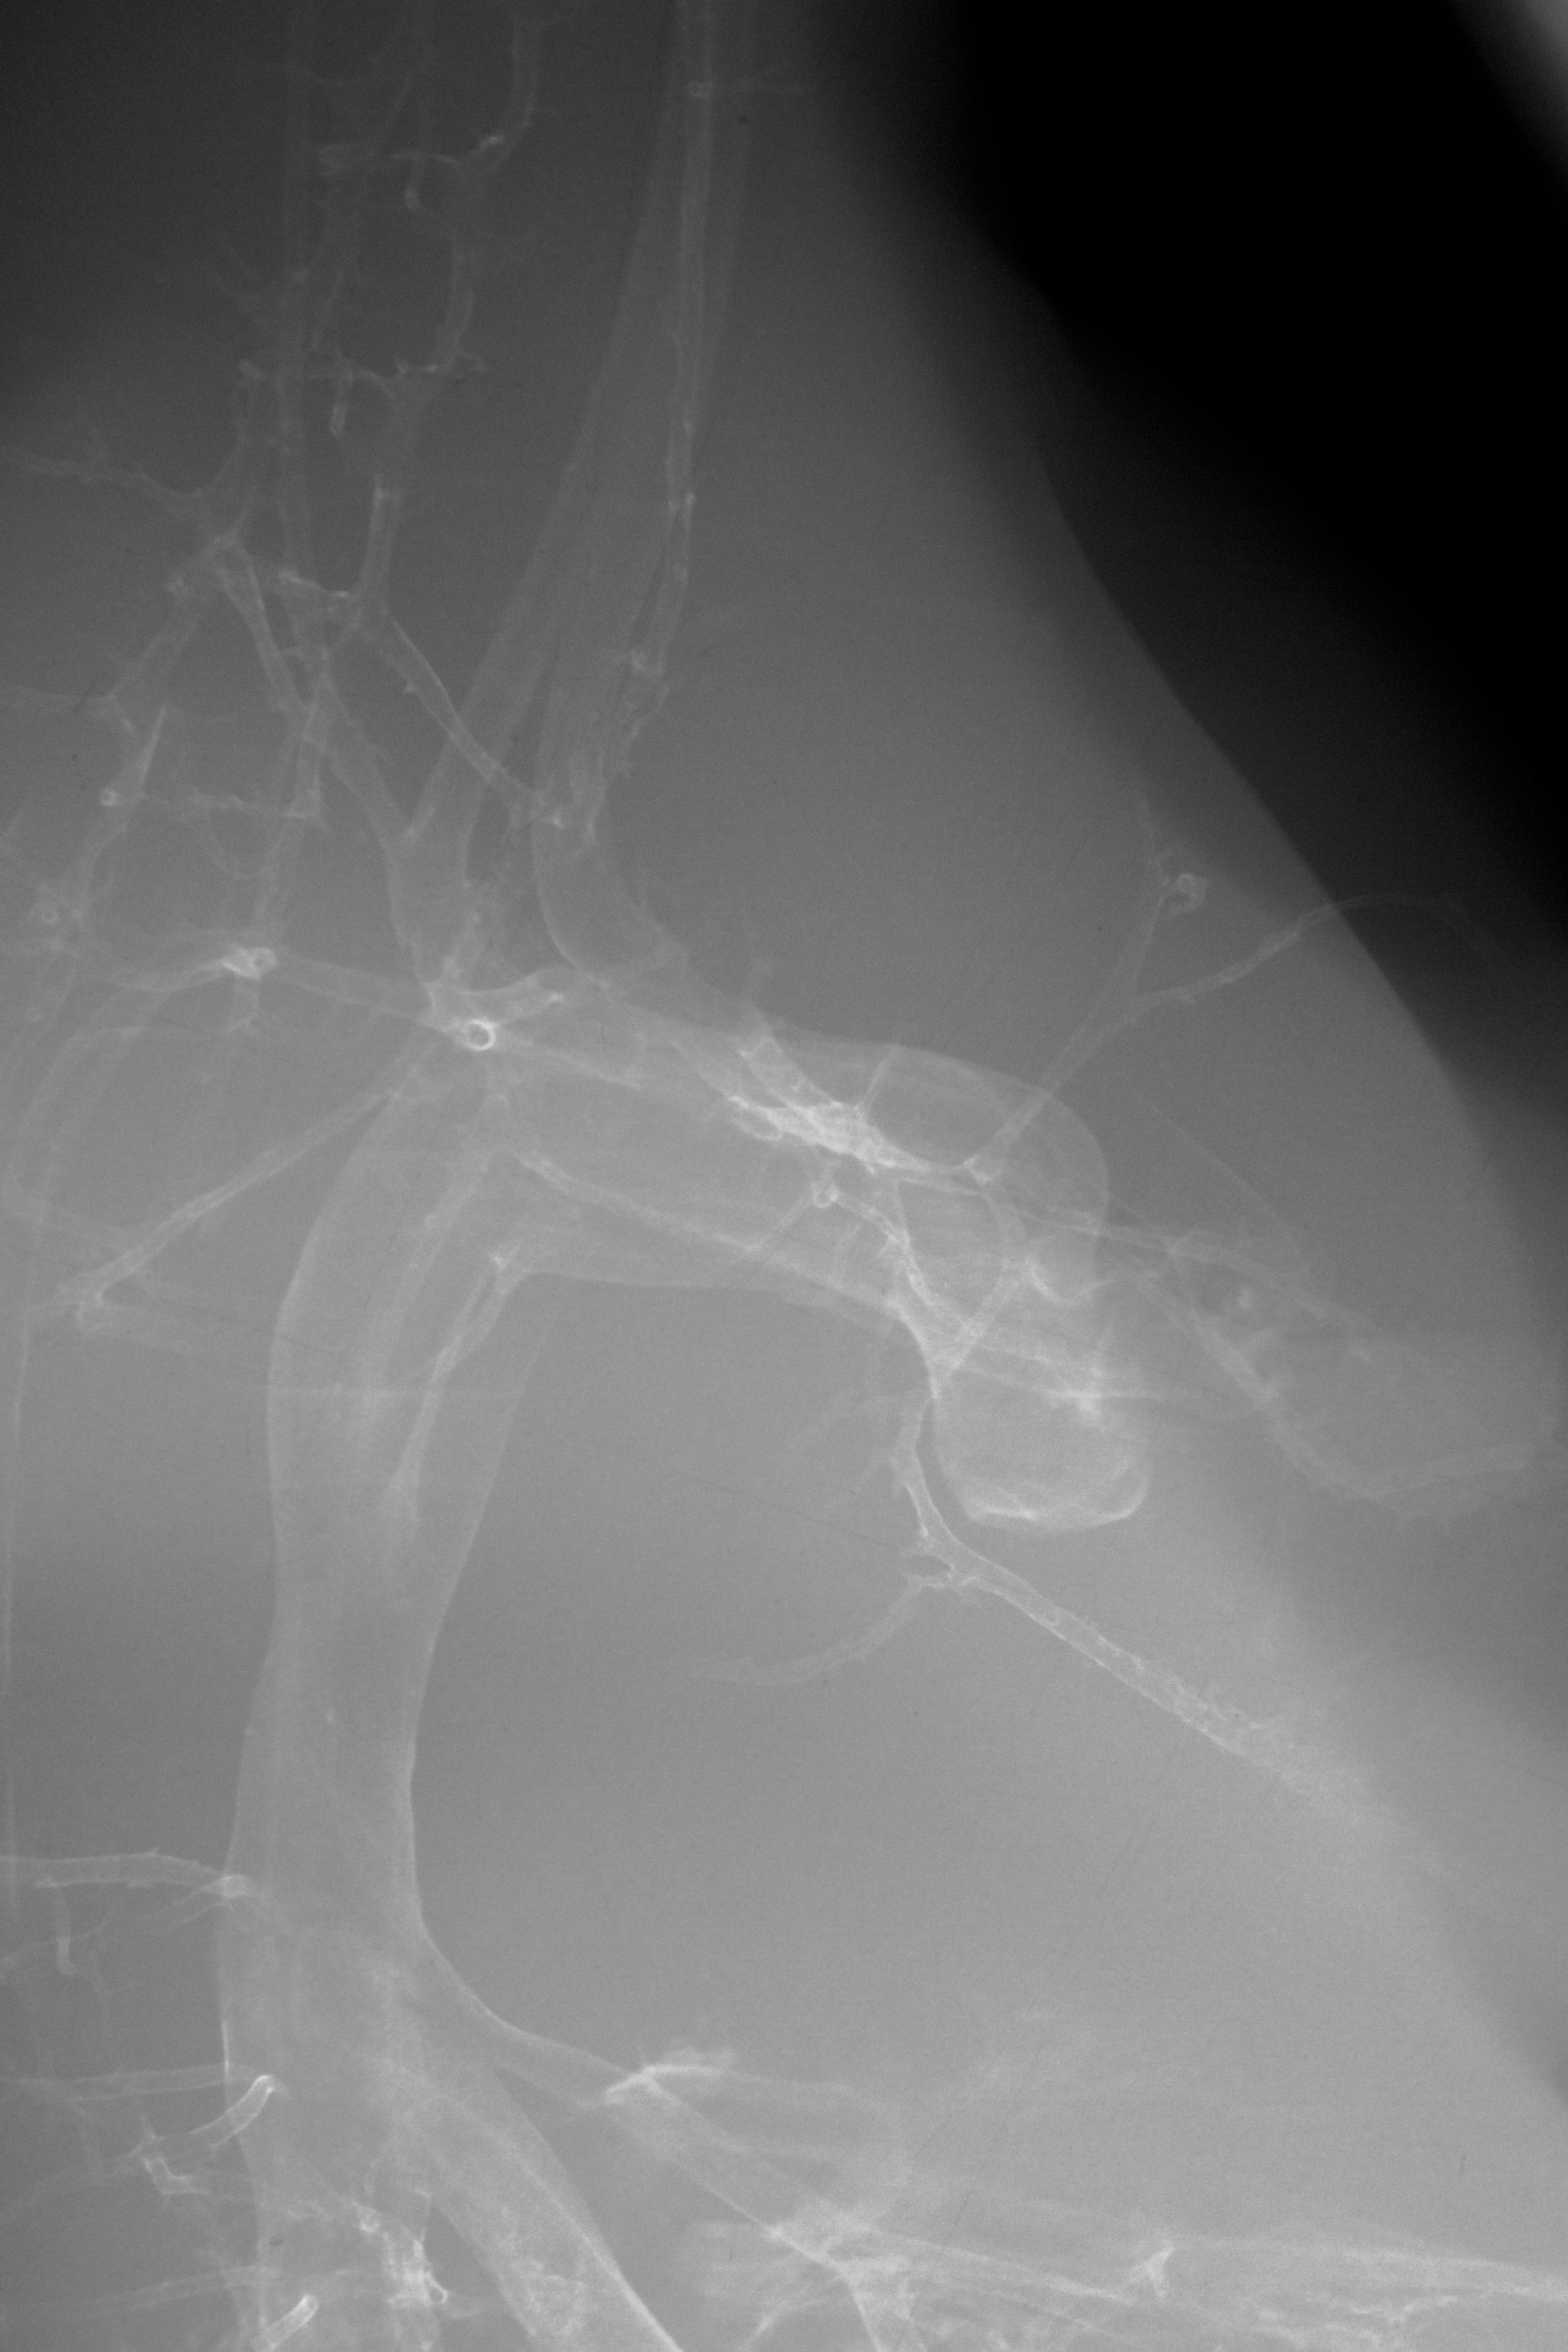

Chick Embryo Microangiography

Hamburger-Hamilton (HH) Stage 35 (approx. 8.5 - 9 days)

Stereo X-Ray Micrographs